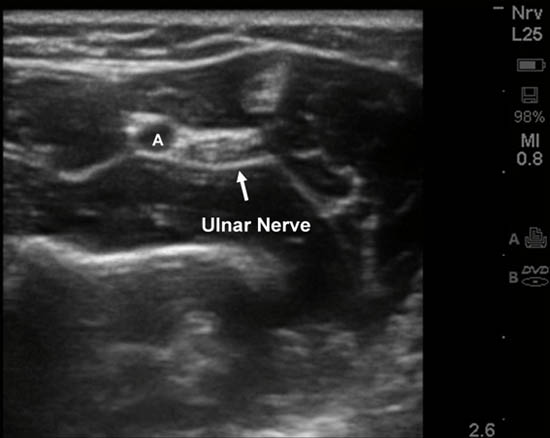

Ultrasound guidance for ulnar nerve block is best performed at the mid forearm where it is more easily seen.[3] At this level, the nerve is medial to the ulnar artery and proximal to the origin of its dorsal branch, thus ensuring adequate blockade. A 5 mL solution of local anesthetic should be injected around the nerve to ensure a complete block (Figure 7).

Figure 7. Ultrasound-guided ulnar nerve blockade in the forearm.